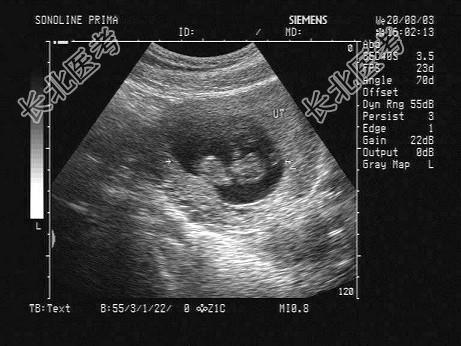

- 单项选择题下图为宫内孕囊声像图,可见心管搏动, 该胎儿至少大于多少周 ( )

A、9周

B、12周

C、10周

D、8周

E、6周